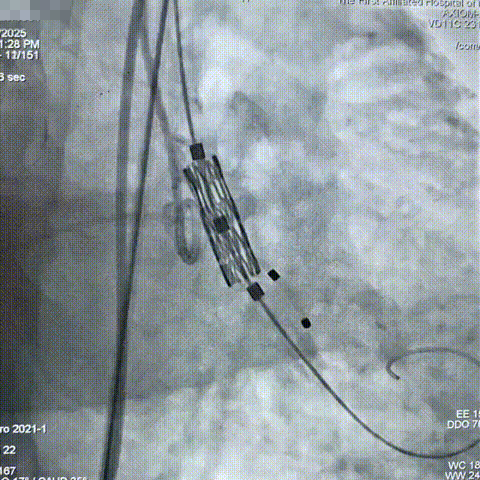

交换超硬导丝至左心室,经右股动脉送入预装有Myval™ 26mm瓣膜的输送系统,成功完成跨瓣操作到达主动脉根部,调整释放深度;

参考术前CT测量值,调整瓣膜至释放前最佳高度,缓慢释放近1/3长度时复查主动脉根部造影,确认瓣膜高度适合,临时起搏180次/分,以80:20比例23±1mL快速释放瓣膜至瓣膜工作区完全打开,于标准位置释放瓣膜;